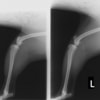

■ 症例24 キャバリア 7か月

左右膝蓋骨内方脱臼(左:グレードⅣ 右:グレードⅢ)

以前から左右後肢の跛行が認められ、整形外科学的検査・レントゲン検査により左右の膝蓋骨脱臼が認められた。症状が重度である左膝の膝蓋骨脱臼整復術を行った。外科手技は縫工筋及び内側広筋の解放、脛骨粗面の外側転位、滑車ブロック形造溝術、内外側関節方の縫縮を実施した。術後一か月時点で、左の膝蓋骨は安定しており経過は良好である。

本症例は成長期における重度の膝蓋骨脱臼であり、術後の再発の可能性もあるため、経過をしっかりと観察していく必要がある。また、今回手術を実施していない右膝に関しても経過を観察し、手術を検討していくこととする。